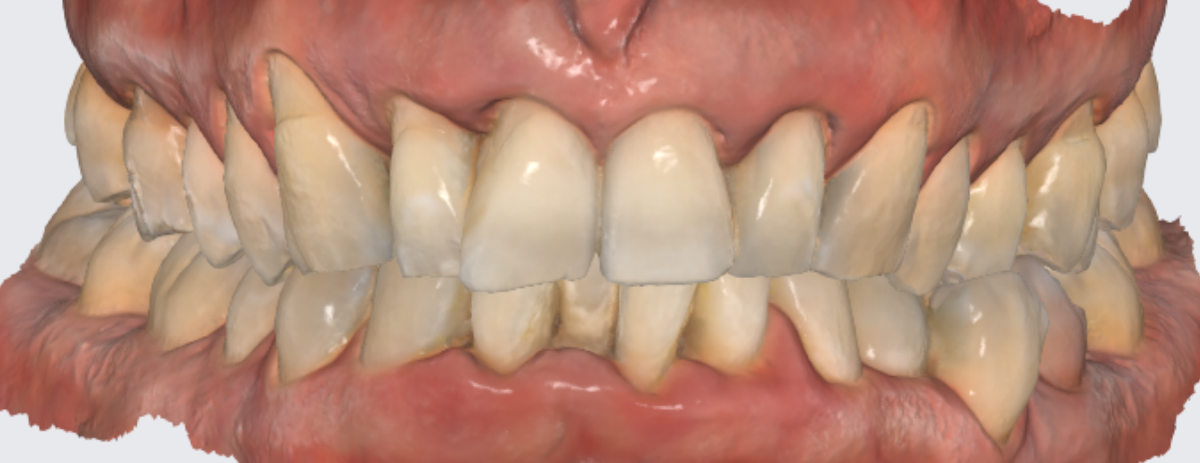

Цифровой слепок.

Как вам результат 3Д сканирования? Ничего не предвещает беды, не правда ли?

Это не похоже на тот пародонтит, который я всем показывала раньше.

А я скажу, что разницы особой нет в состоянии кости. Пародонтит тяжёлой степени тяжести может выглядеть и так, и так.